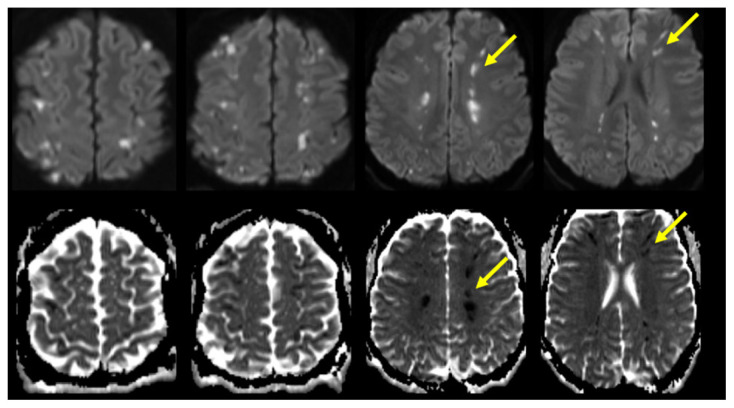

Acute Border Zone Infarcts in Hypereosinophilic Syndrome.